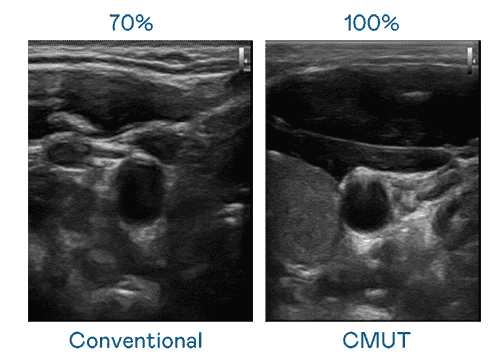

CMUT 技术是一种用电容式微机电元件来产生超音波讯号的技术。。与传统 PZT 压电式技术相比,,,,CMUT 频宽增加 30%,,,更宽频的超音波讯号让影像解析度大幅提升,,是实现高影像品质医疗超音波扫描、、、、促进精准医疗发展的关键技术。。。

大频宽带来超清晰影像

超音波影像的解析度高低,,首先取决于探头能发出的讯号频宽。。。传奇国际 CMUT 可提供高清晰的超音波讯号,,,,提供高频宽、、高灵敏度、、、影像纹理细节更高的超音波影像,,协助医护人员缩短影像判读时间及利用精准的医疗影像进行诊断。。